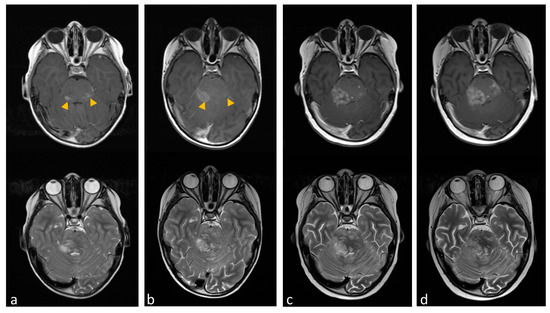

2.4. The Clinical Use of Miglustat in Two Patients with H3K27M-Mut DMG